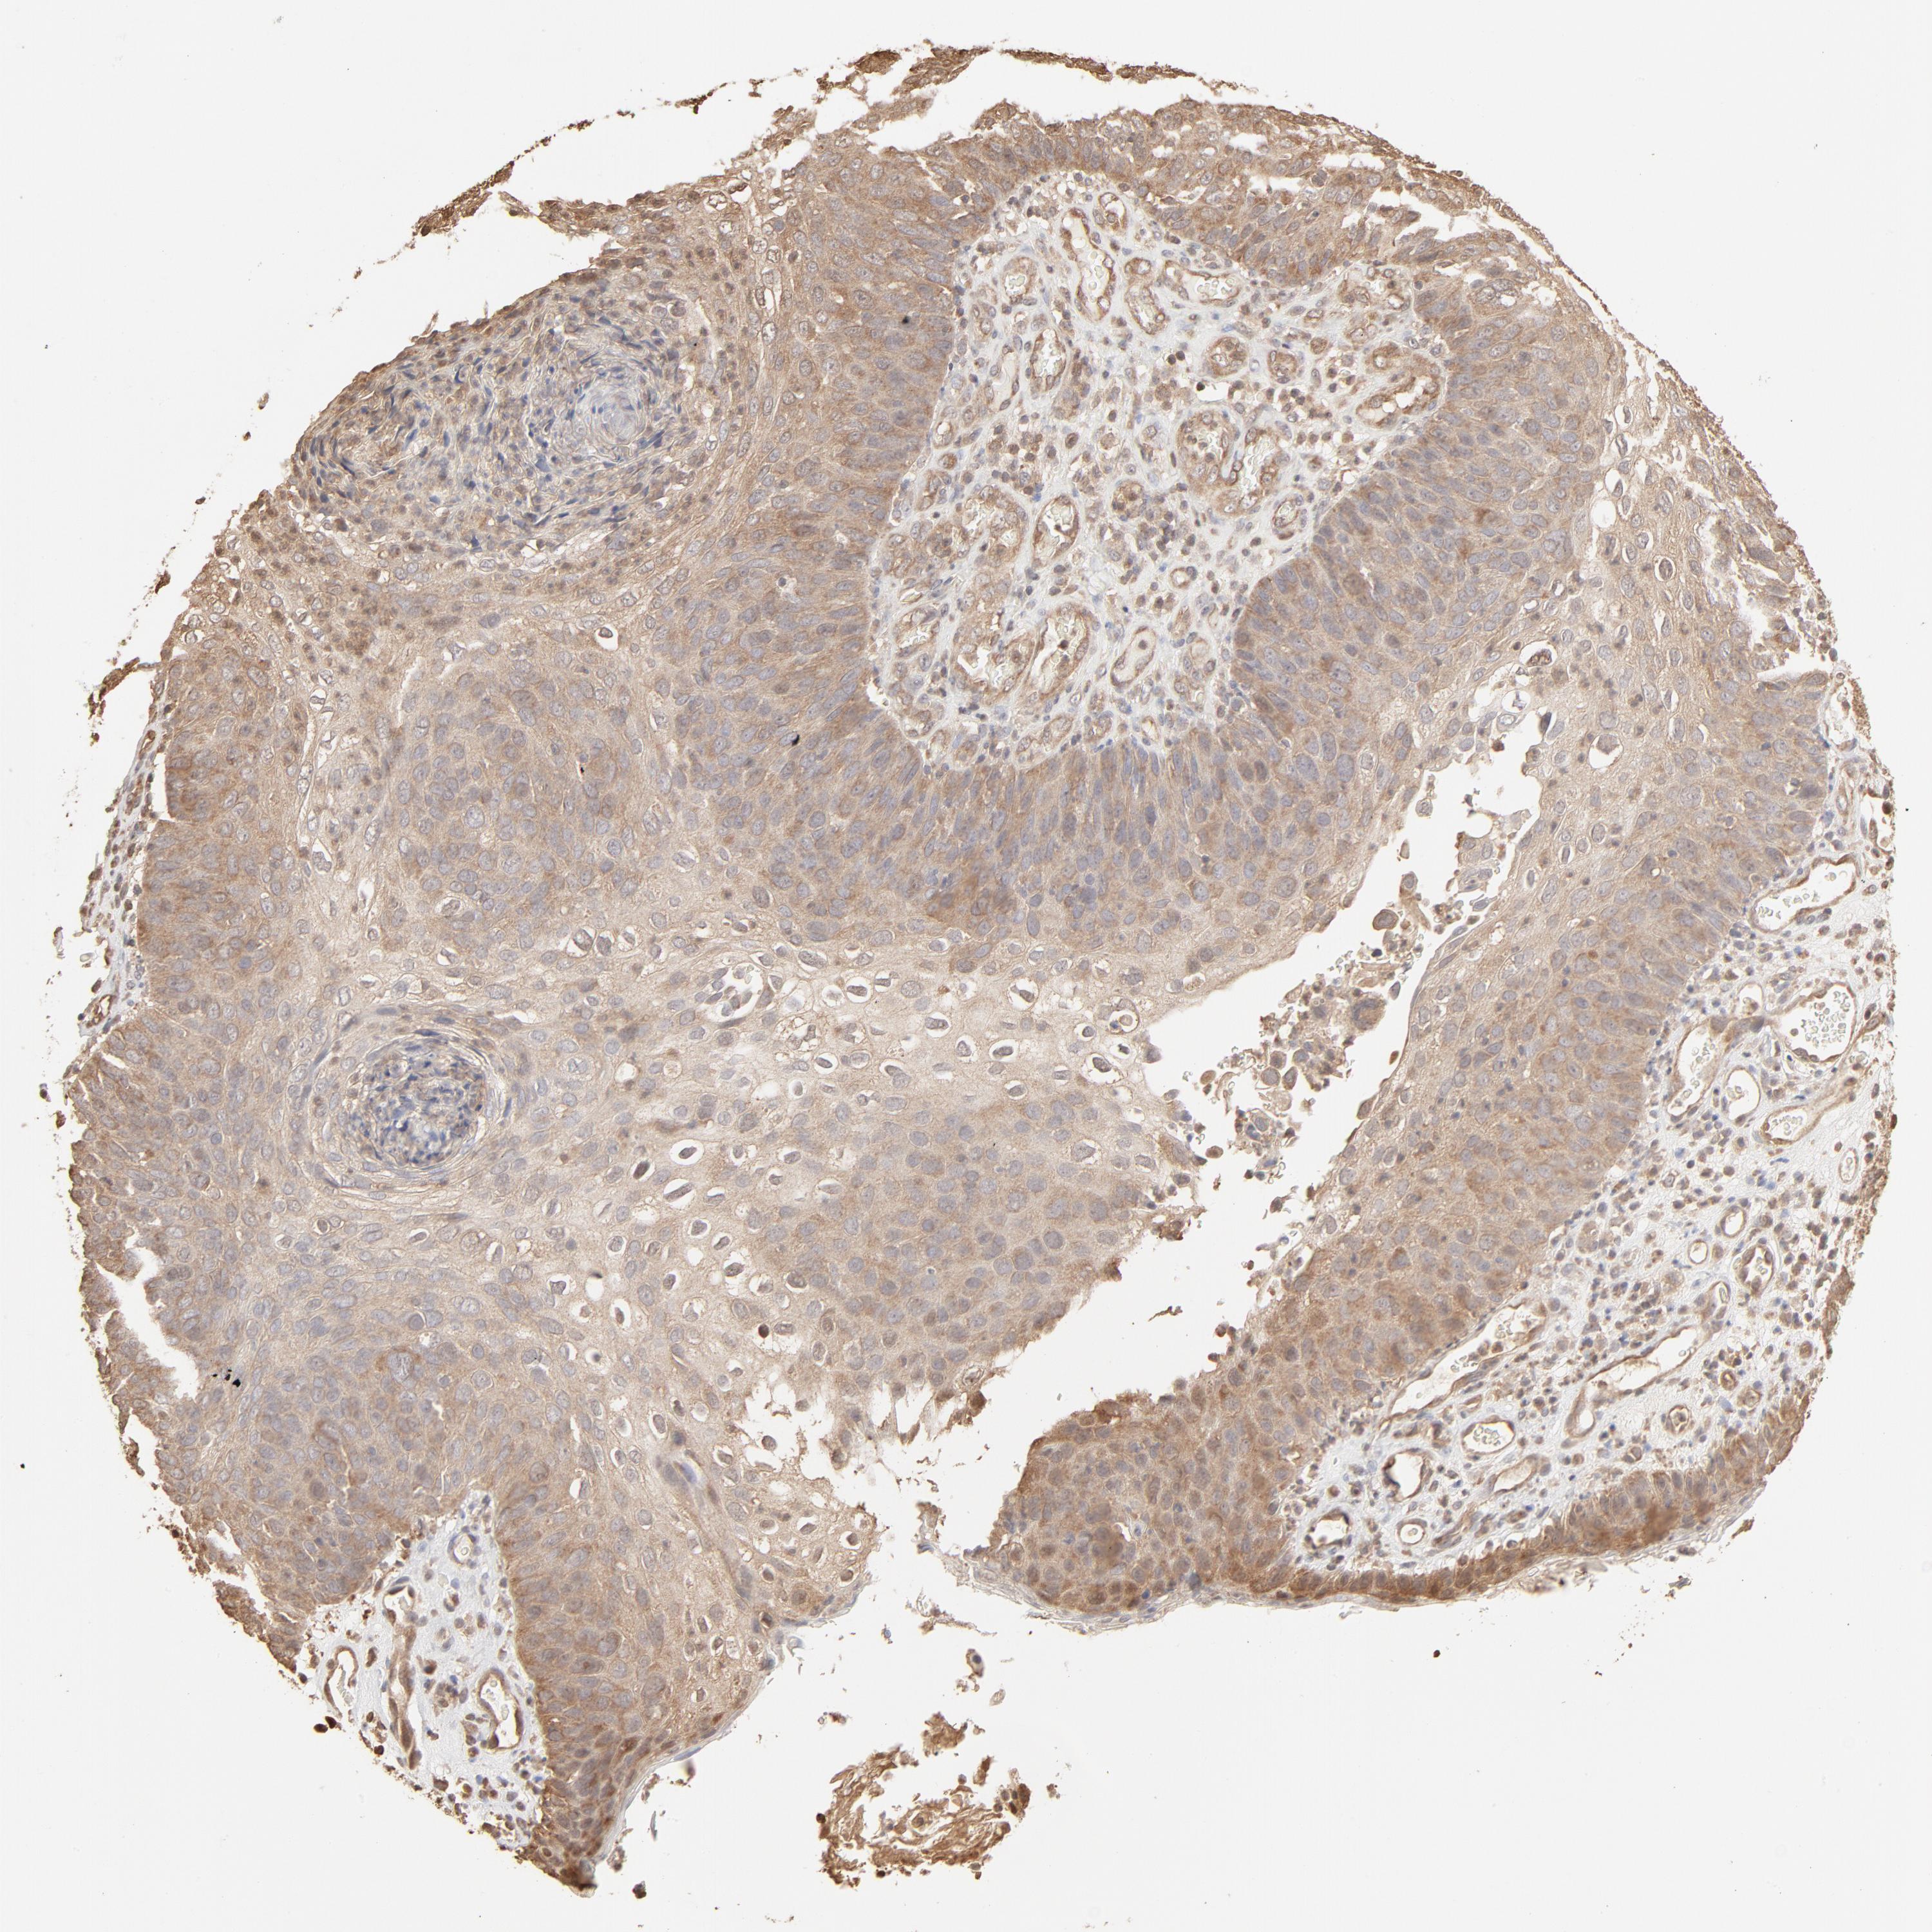

SKIN CANCER - Protein expressioni

A mouse-over function shows sample information and annotation data. Click on an image to view it in a full screen mode. Samples can be filtered based on level of antibody staining by selecting one or several of the following categories: high, medium, low and not detected. The assay and annotation is described here.

Antibody stainingi

Antibody staining in the annotated cell types in the current human tissue is reported as not detected, low, medium, or high, based on conventional immunohistochemistry profiling in selected tissues. This score is based on the combination of the staining intensity and fraction of stained cells.

Each image is clickable and will lead to virtual microscopy that enables deeper exploration of all samples and also displays staining intensity scores, fraction scores and subcellular localization as well as patient and tissue information for each sample.

Antibody CAB003848

Squamous cell carcinoma, metastatic, NOS

Squamous cell carcinoma, NOS